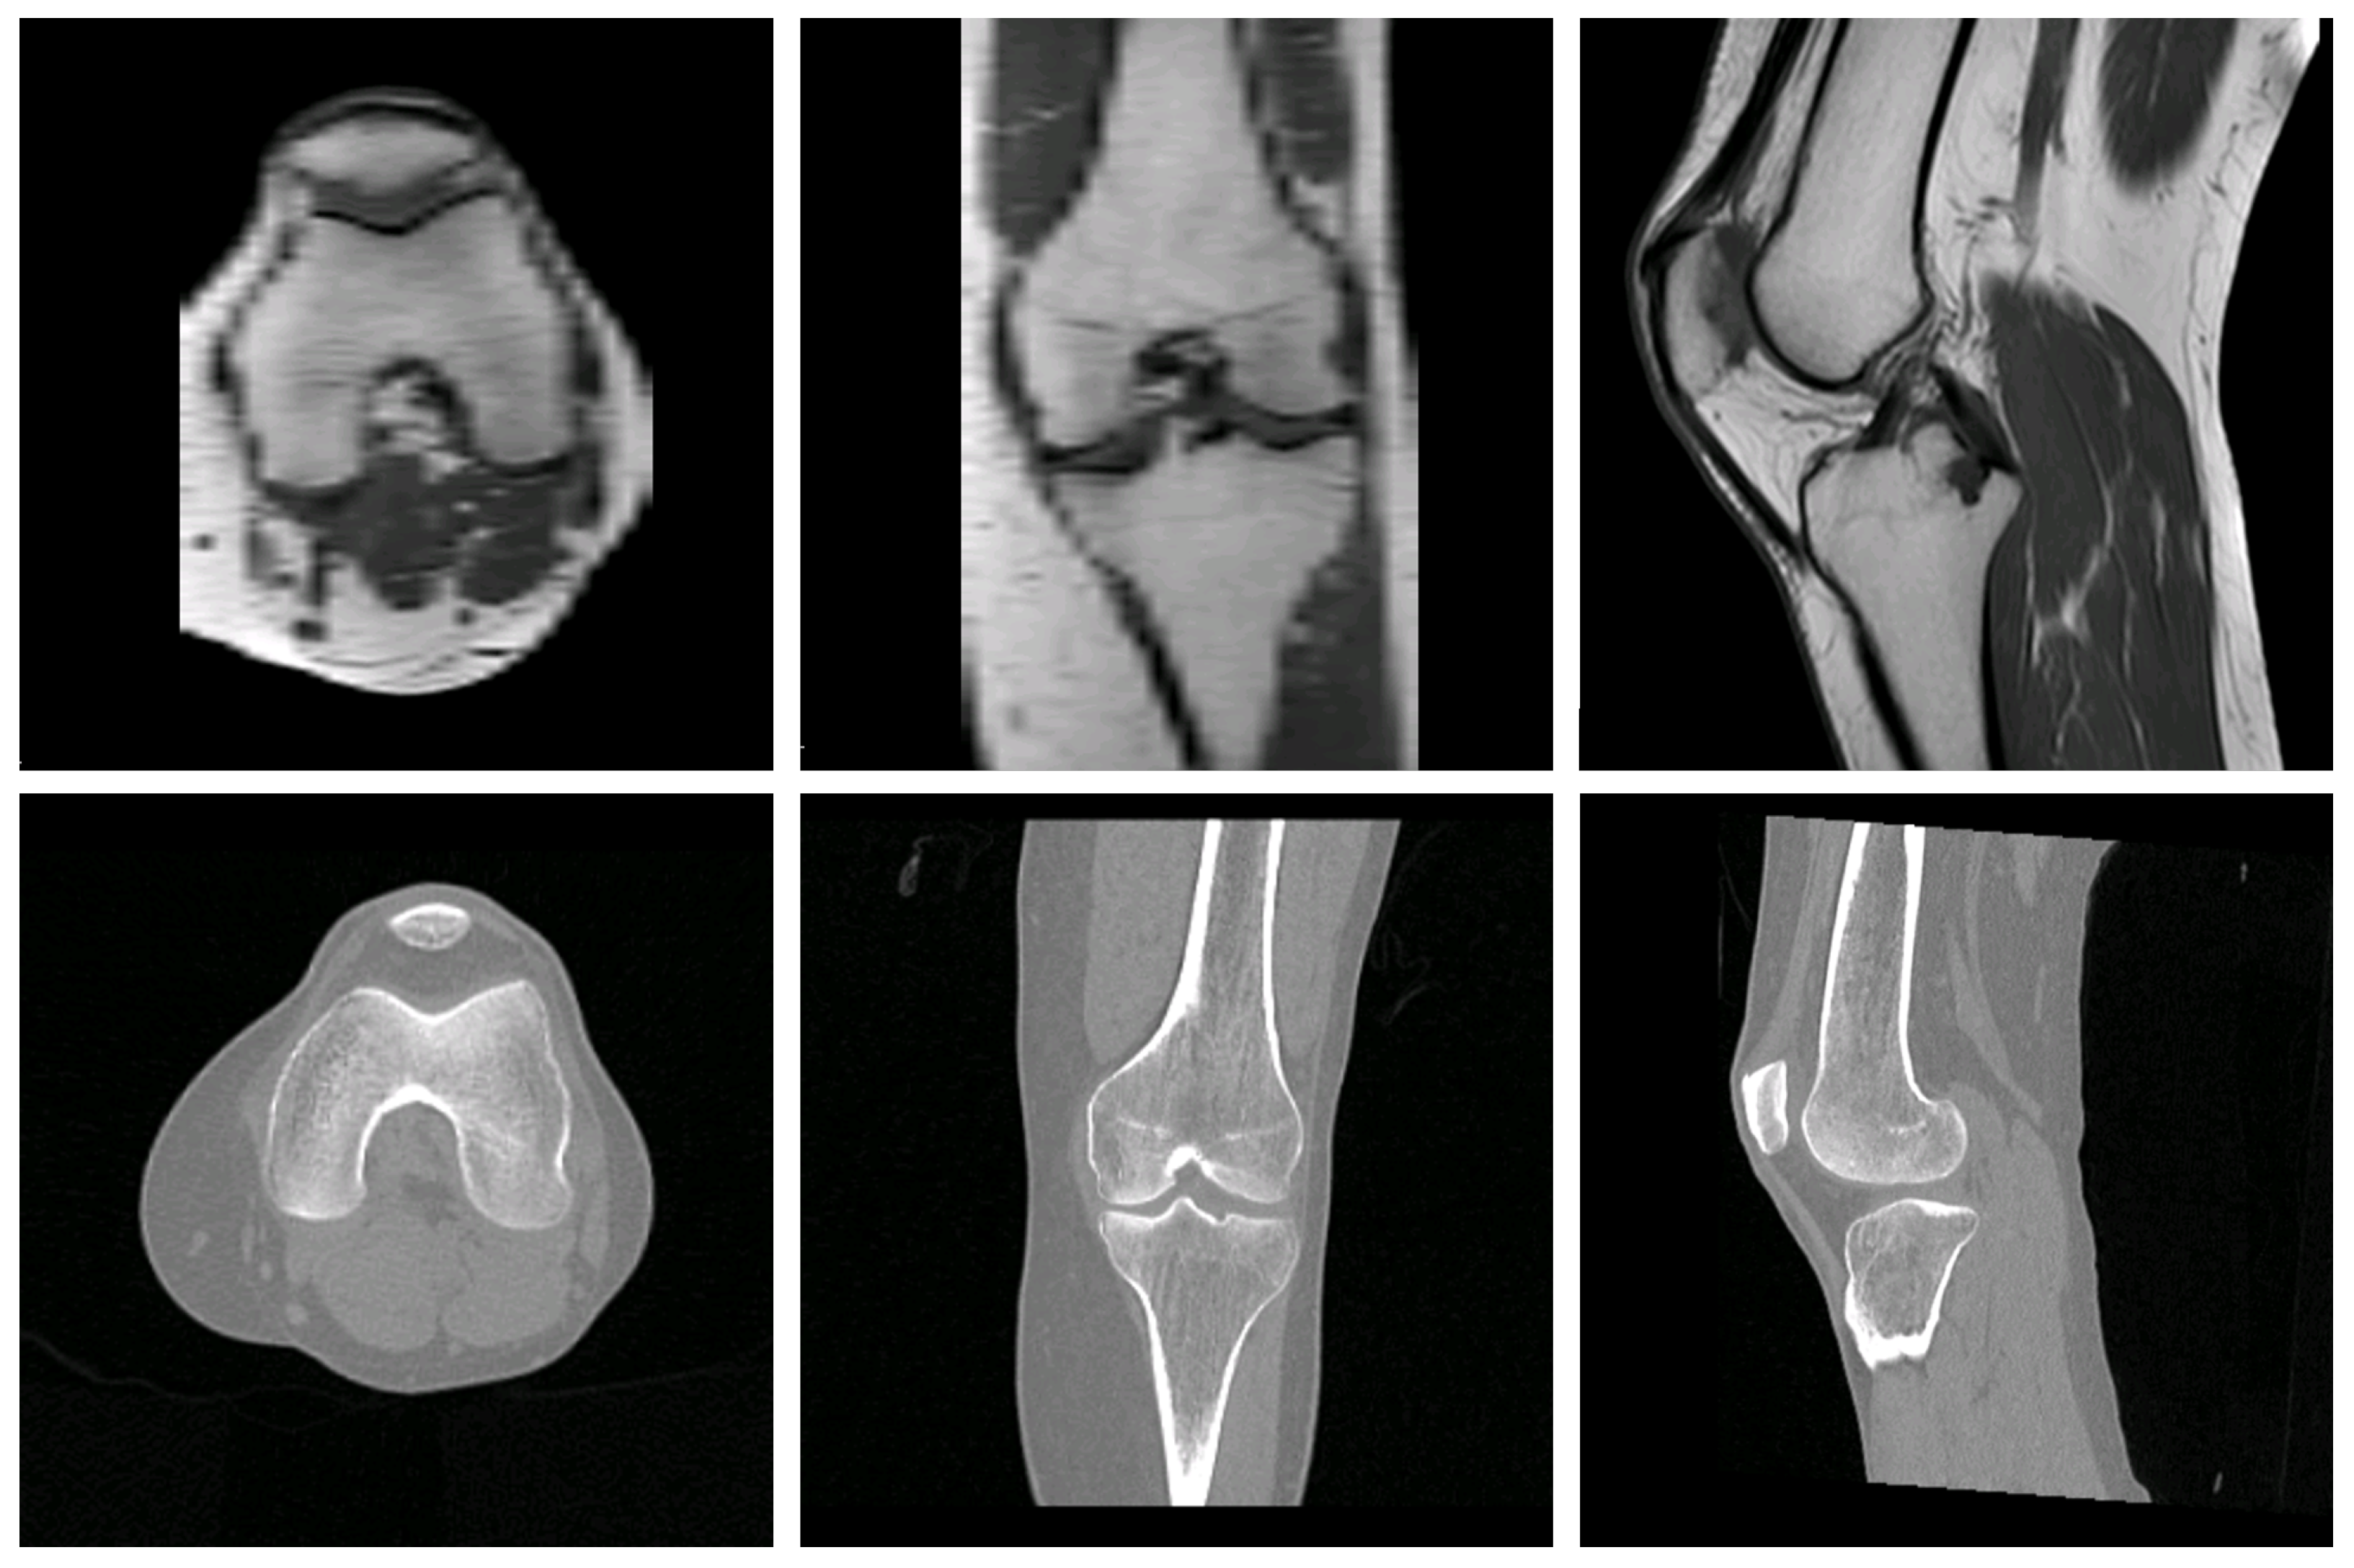

3.1. Qualitative Results